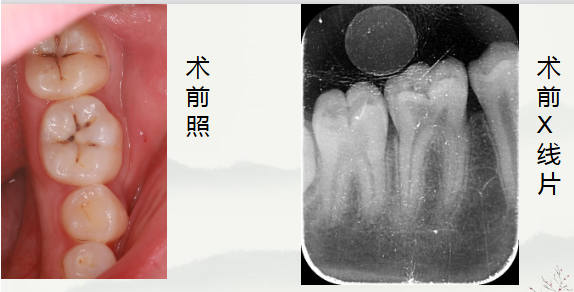

通过术前照与X线片,小牙片可见,颌面龋坏,远中邻面龋坏,叩+,松动-,

夜间自发痛,冷热刺激与对照牙对比反应明显。诊断为急性牙髓炎